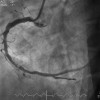

Dalam pedoman ini, sindrom koroner kronis didefinisikan sebagai serangkaian presentasi klinis atau sindrom yang muncul akibat perubahan struktural atau fungsional yang terkait dengan penyakit kronis pada arteri koroner. Presentasi mencakup pasien asimtomatik dengan hasil tes anatomi atau fungsional abnormal, angina tanpa penyakit arteri koroner (PJK) obstruktif, stress-induced angina dengan PJK obstruktif, dan penyakit stabil setelah sindrom koroner akut, kateterisasi, atau operasi by pass, serta disfungsi ventrikel kiri atau gagal jantung akibat iskemia.[1]